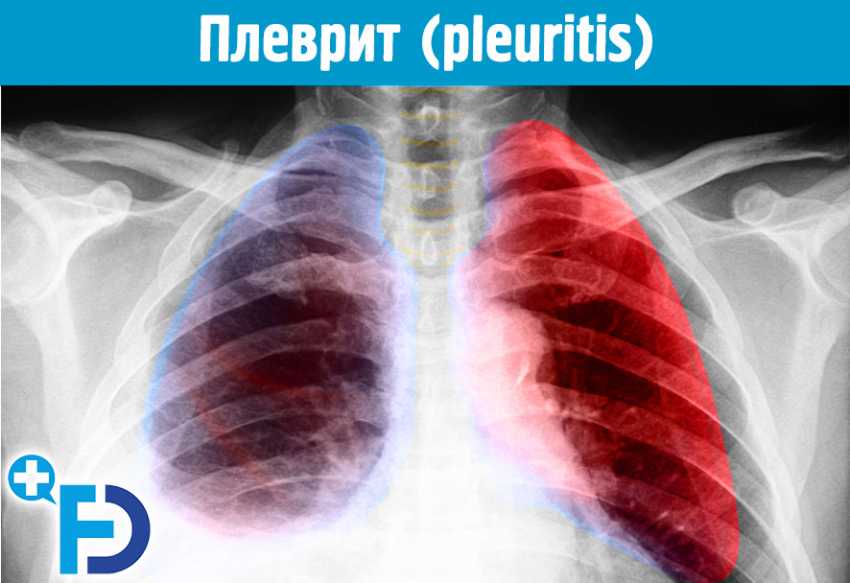

Диагностика плеврального выпота: что нужно знать